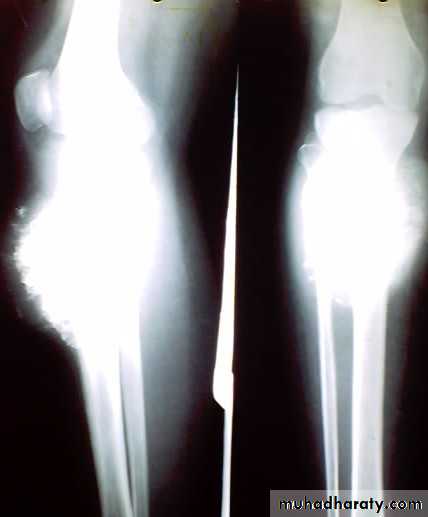

Giant cell tumor

Patient presented by local pain and swelling or pathological fractures. Common site is the distal femur, proximal tibia, distal radius.

X-ray show eccentric osteolytic lesion in the end of long bone ,subchondral, trabeculated (soap bubble appearance). The cortex is thin, expanded or even perforated.